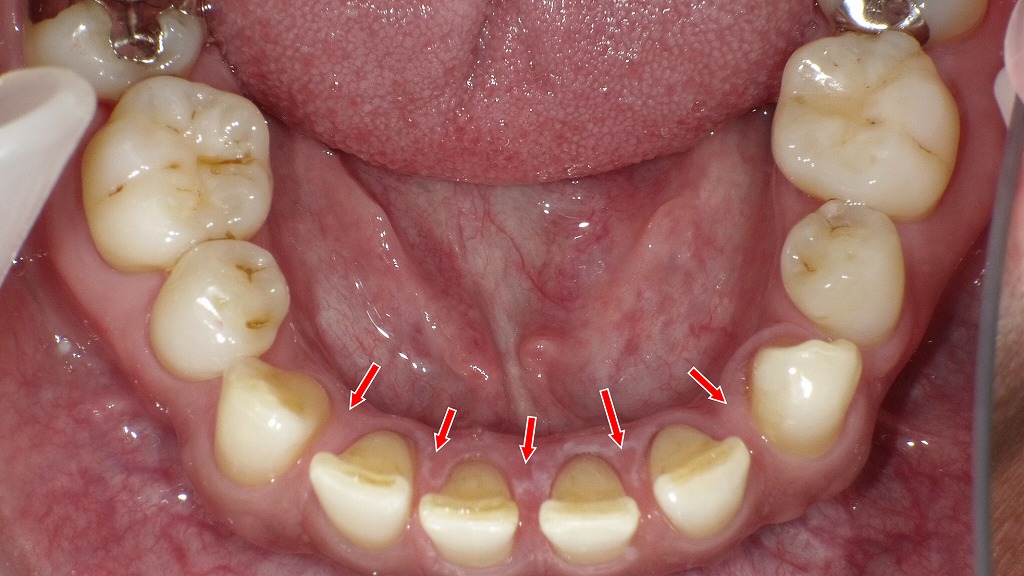

【正面観と下顎咬合面観】

下顎の左右第一小臼歯(4番)が先天欠損(上顎は正常)しており、その影響で下顎前歯部にすき間(空隙歯列)が生じている症例です。欠損により歯列の連続性が途切れ、噛み合わせや前歯の並びに特徴的な変化が見られます。